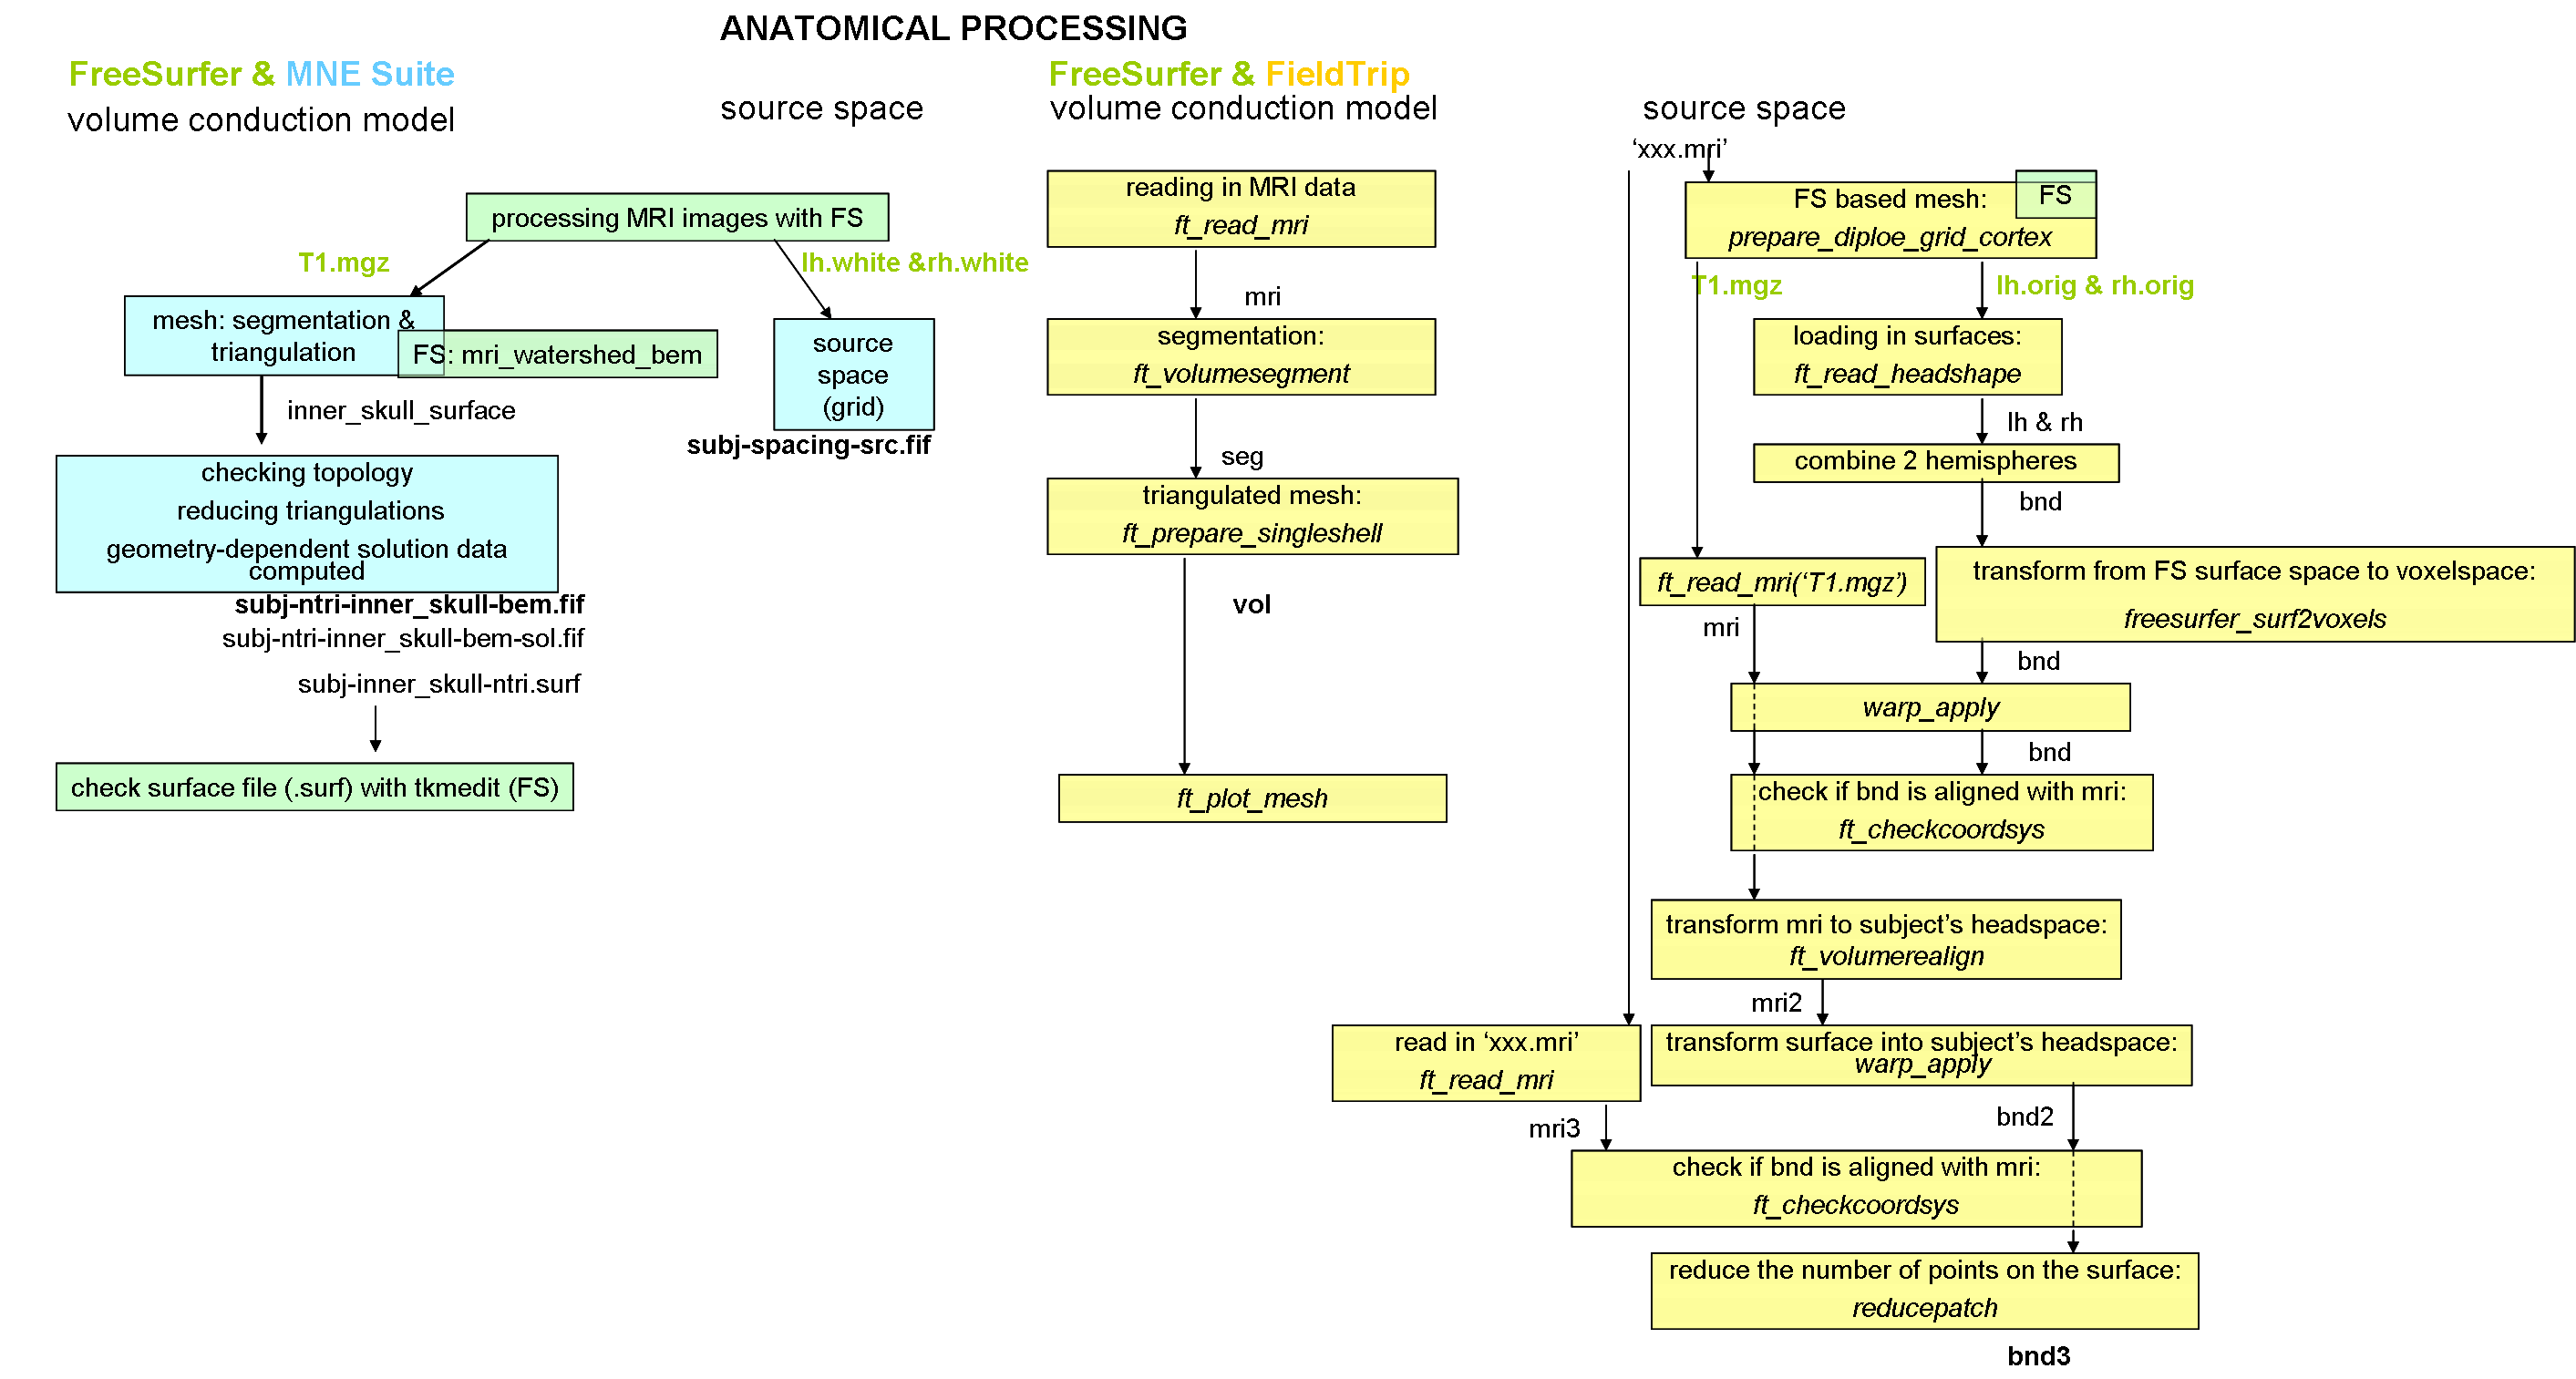

1. Anatomical processing

The first part of anatomical processing of the MRI data is done by the FreeSurfer program. MNE is using the output of this program and one of the FS functions to create head shapes with the boundary element method (BEM) and to set up the source space for the forward solution. The next figure shows the filenames (with red) that were created by FS and MNE is using them for input. When MNE is creating the BEM model meshes it is using a function (mri_watershed) from FS. Therefore, the FS has to be set up before running this MNE function.

The following figure shows the MNE and FS and FT pipeline of anatomical processing.

–0)